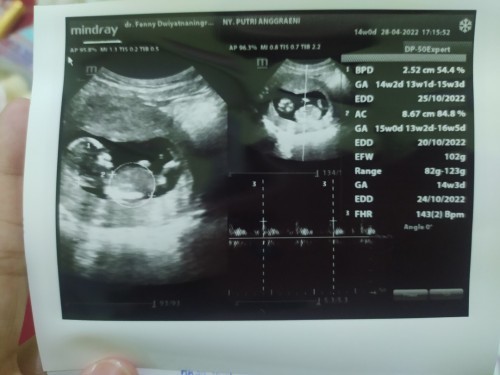

Hasil usg kehamilan 3bulan

Bantuin bacain hasil usg dong bun

BPD: perkembangan diameter kepala: 2.52cm GA: usia kehamilan di gambar 1: 14minggu2 hari, di gambar 2: 15 minggu AC: lingkar perut: 8.67cm EDD: HPL atau hari perkiraan lahir di gambar 1 25/10, gambar 2 24/10 EFW: BB janin: 102 gram FHR: DJJ atau detak jantung janin 143(2) Bpm